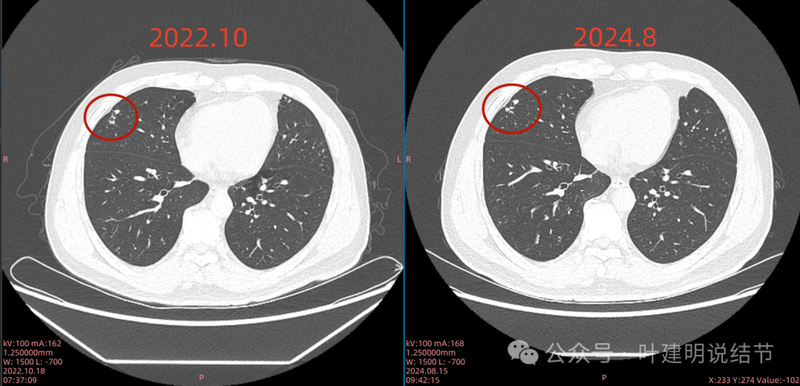

与既往对比影像:

2022年10月主病灶处没有异常。

2022年时右中叶处本来就有的。

右上这个结节实性,有血管征的样子,整体轮廓较清,如果从单次来看,是要考虑恶性可能性稍大些的,何况对比2022年时此灶不明显,那是新增的。但我觉得总体上看,倾向良性的一些:1、两肺,尤其是右中叶有多发斑点状实性小结了,较为散在,且对比2022年时无明显进展,说明肺部存在感染性的情况过,他处是遗留有慢性炎或肉芽肿性病变的基础在的,那么主病灶也是同样性质的可能性就增大了;2、冠状位与矢状位看,病灶的瘤肺边界不是很清楚,不像横断面上清楚,说明炎性的可能性是有的;3、实性病灶,但在纵向看,邻近血管并没有受到牵拉影响,没有形成血管弯征,说明收缩力或侵袭性不够。再加上病灶仍小,我的想法是考虑良性可能性大,并建议先4-6个月再复查下,期间也可试试口服莫西沙星消炎10-12天,若更进一步,也可查查结核与隐球菌方面的化验。意见供参考!